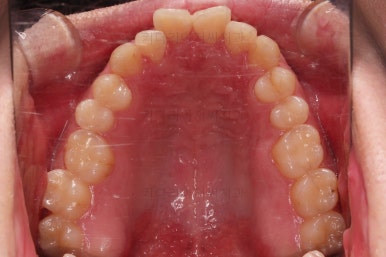

우선은 악궁확장장치를 합니다.

아무튼 이번 환자분은 위턱 자체가 폭이 좁아서 확장을 먼저 진행했고요.

확장 이 후 유지 기간동안 다른 치열을 가지런하게 해줍니다.

수술 전 교정과정이 거의 마무리 되어 갑니다.